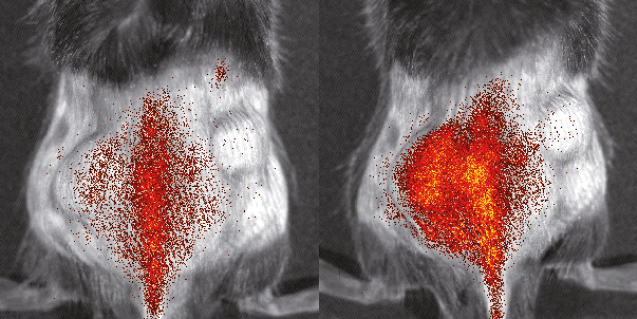

Bildgebung von markierten Monozyten während eines Herzinfarkts© EIMI/M. Schäfers Combining myeloid precursor immortalization, genome editing and genetic reporter systems for imaging of monocyte trafficking in inflammation and ischemia

Förderkennzeichen: DA 1064/3-1 | DFG EinzelförderungMonitoring molecular mechanisms of monocyte migration during inflammatory processes in vivo

Projektleitung: Michael Schäfers (EIMI), Johannes Roth

Projektlaufzeit: 07/2013 - 06/2015

Förderkennzeichen: EXC 1003 FF-2013-24 | DFG Exzellenzcluster "Cells in Motion"Regulation adulter Neurogenese durch inflammatorische Prozesse